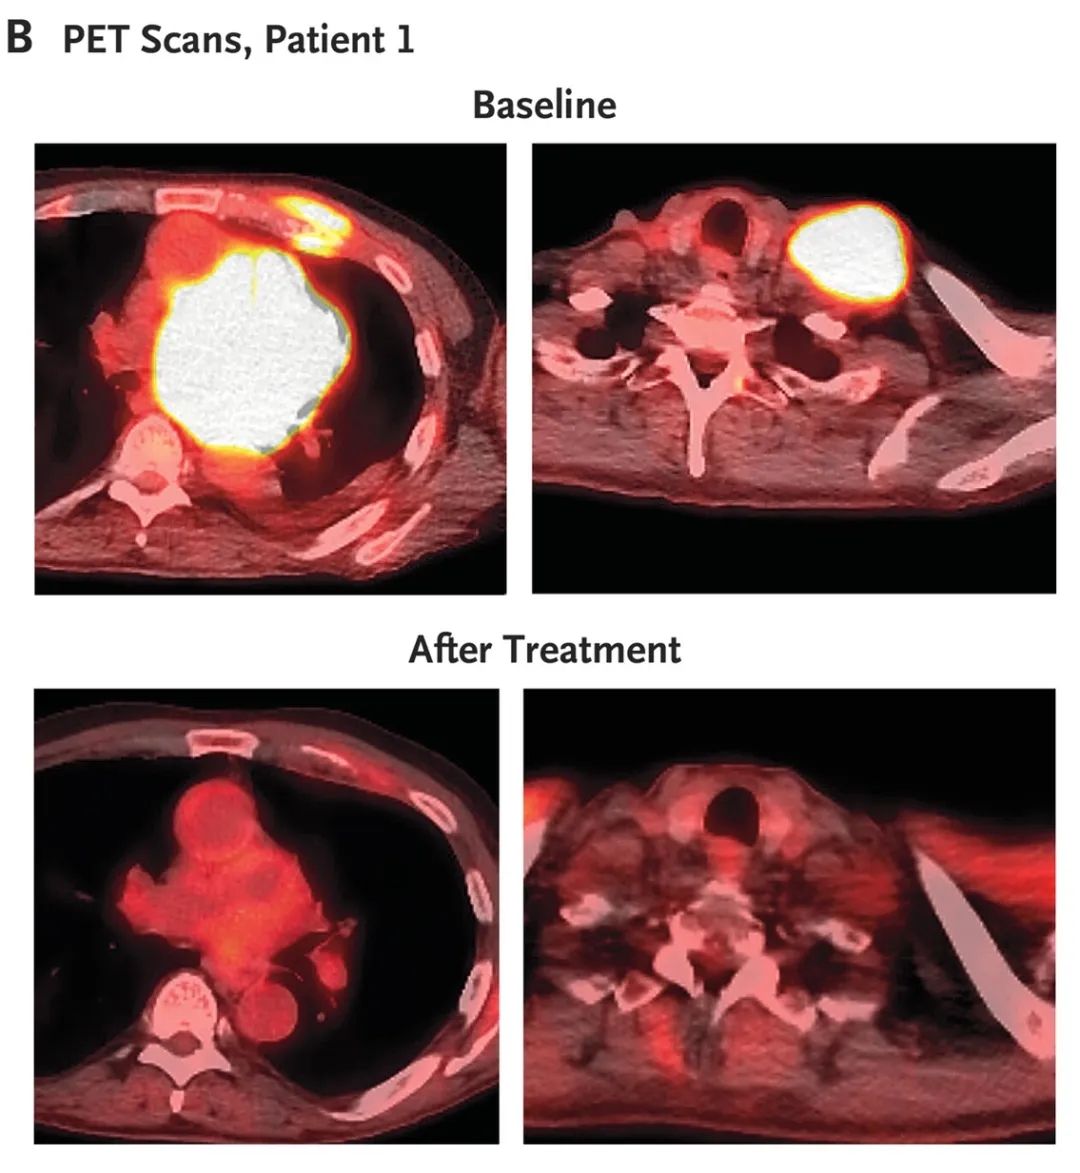

值得一提的是,下图展示了接受25×10⁶个CAR-T细胞治疗的患者1,在基线和治疗后的正电子发射断层扫描(PET)图像(详见下图B)。

▲图源“N Engl J Med”,版权归原作者所有,如无意中侵犯了知识产权,请联系我们删除